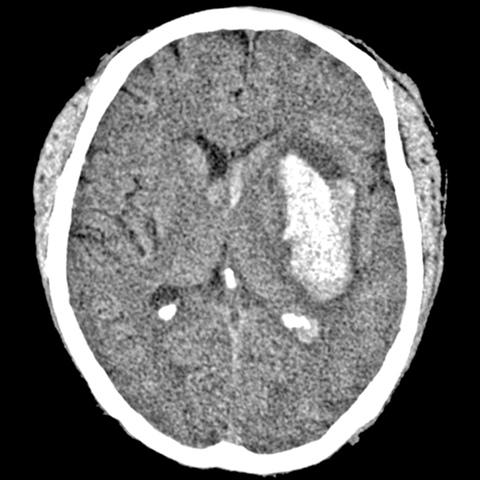

Intracranial Hemorrhage, Spontaneous [3 of 3]